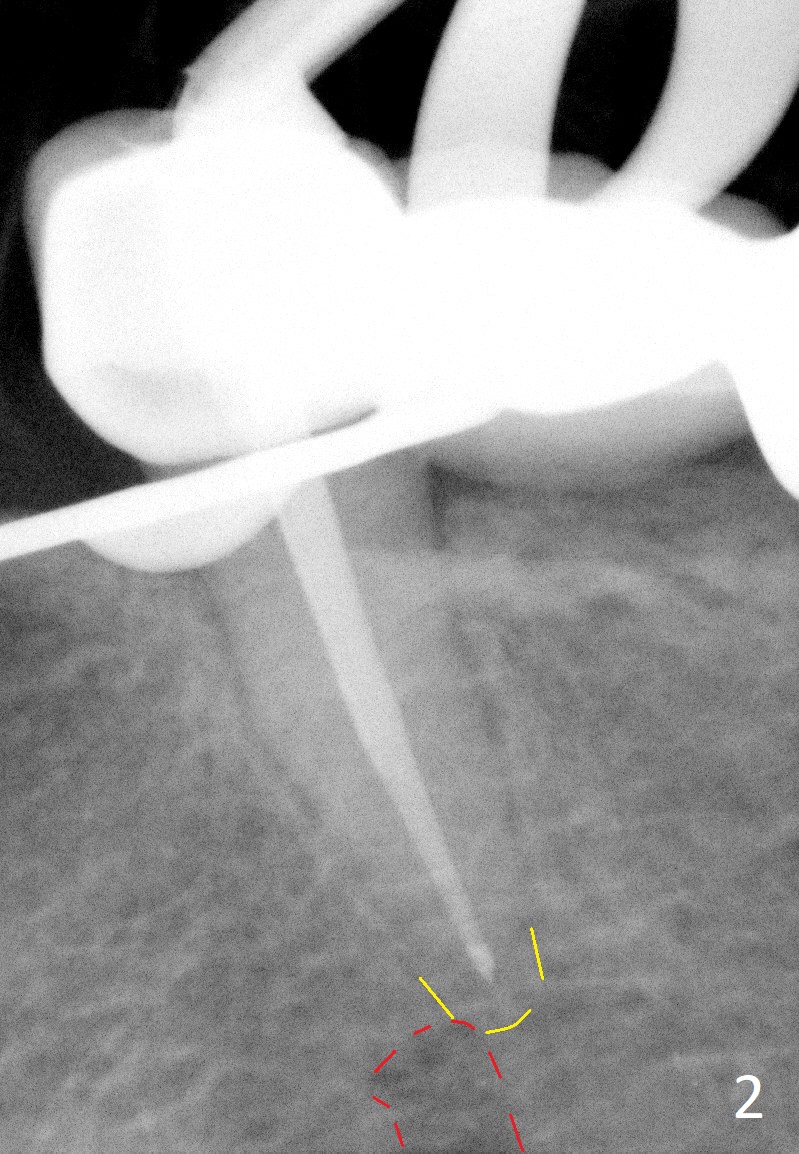

A 65-year-old woman used to have a long bridge (Fig.1). First, the portion mesial to #20 was sectioned. But the remaining portion kept chipping. RCT was retreated for the tooth #20 as the first step to have separate crowns at #18 and 20 and have a lower partial redo. Instead a new FPD was done between #18 and 20 in her own country (Fig.2). Two years later, the tooth #20 became symptomatic with increased pdl mesially (Fig.3*). Periradicular radiolucency increases in another 2 years (Fig.4). The apex of the affected tooth (yellow dashed line) is close to the Mental Loop (red dashed line, Fig.1-3). Although the loop is buccal to the apex of the 2nd premolar, an implant will not extend past the apex to avoid neuropathy (Fig.5). No Inferior Alveolar Nerve block will be administered. PA will be taken after pilot drill. The FPD will be sectioned between #18 and 19. To compensate for the short length of the implant, try to place a large one as long as the buccolingual bone allows. Adapt the lower RPD to the immediate provisional, which should be as small as possible, since the retention must be not too high.